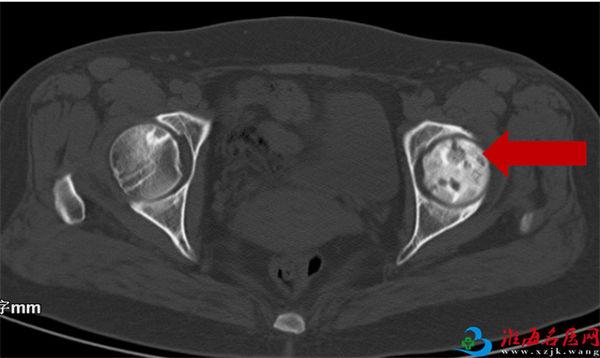

2021年05月20日末次复查CT显示:

右股骨头坏死三期,左股骨头正常